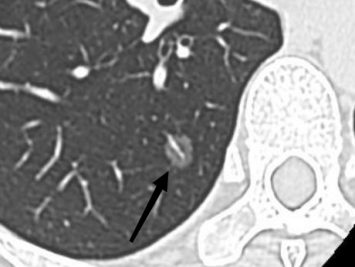

256排高端CT:不仅支持肺部高分辨CT检查,还能在单次扫描中精准诊断急性冠脉综合症、急性肺栓塞和主动脉夹层等危急症状。CT引导下的穿刺活检术也使得精确诊断成为可能,成为胸外科肺结节切除的得力助手。